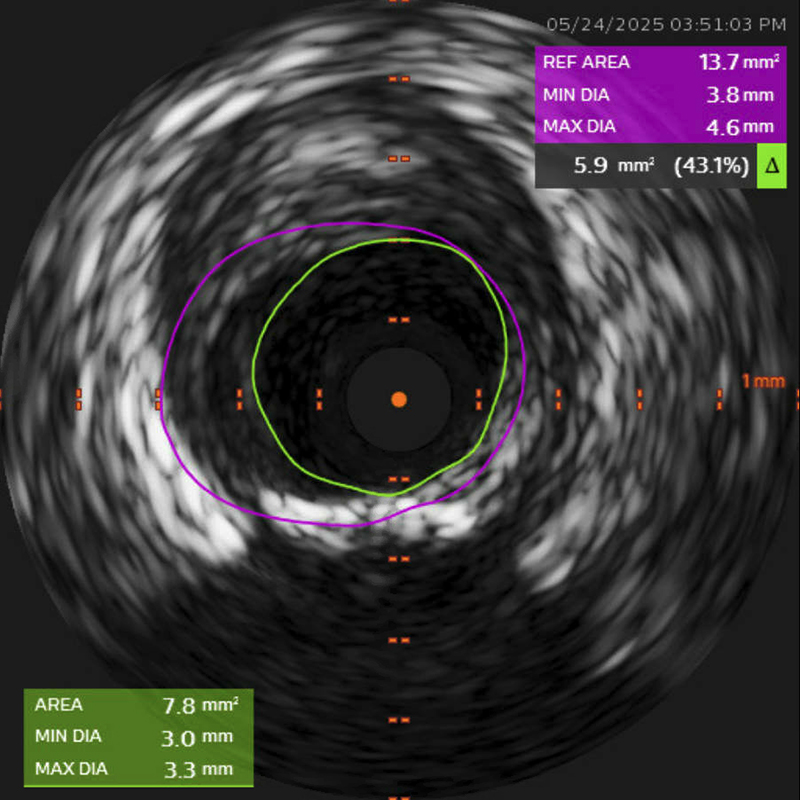

Emergent coronary angiography was performed via radial access. It revealed obstructive coronary artery disease (CAD) with 70% stenosis in the proximal left anterior descending artery (LAD), along with diffuse distal disease, and 80% stenosis in the proximal-to-mid segment of the right coronary artery (RCA) (Figure 2). The distal left main (LM) coronary artery showed 40–50% stenosis; however, intravascular ultrasound (IVUS) demonstrated a minimum luminal area of 7.8 mm2 with 43.1% stenosis (Figure 3). No unstable lesions were identified by intravascular imaging. Percutaneous intervention (PCI) was performed on the LAD using a 3.5 × 18 mm Xience drug-eluting stent (DES), with persistent TIMI-1 flow. The RCA underwent balloon angioplasty with a 2.5 × 20 mm compliant balloon, followed by placement of three Xience DES: 3.5 × 28 mm, 4 × 18 mm, and 3.5 × 8 mm.

Figure 3

Figure 3. Intravascular ultrasound (IVUS). IVUS demonstrated a minimum luminal area of 7.8 mm2 with 43.1% stenosis of the distal left main coronary artery.